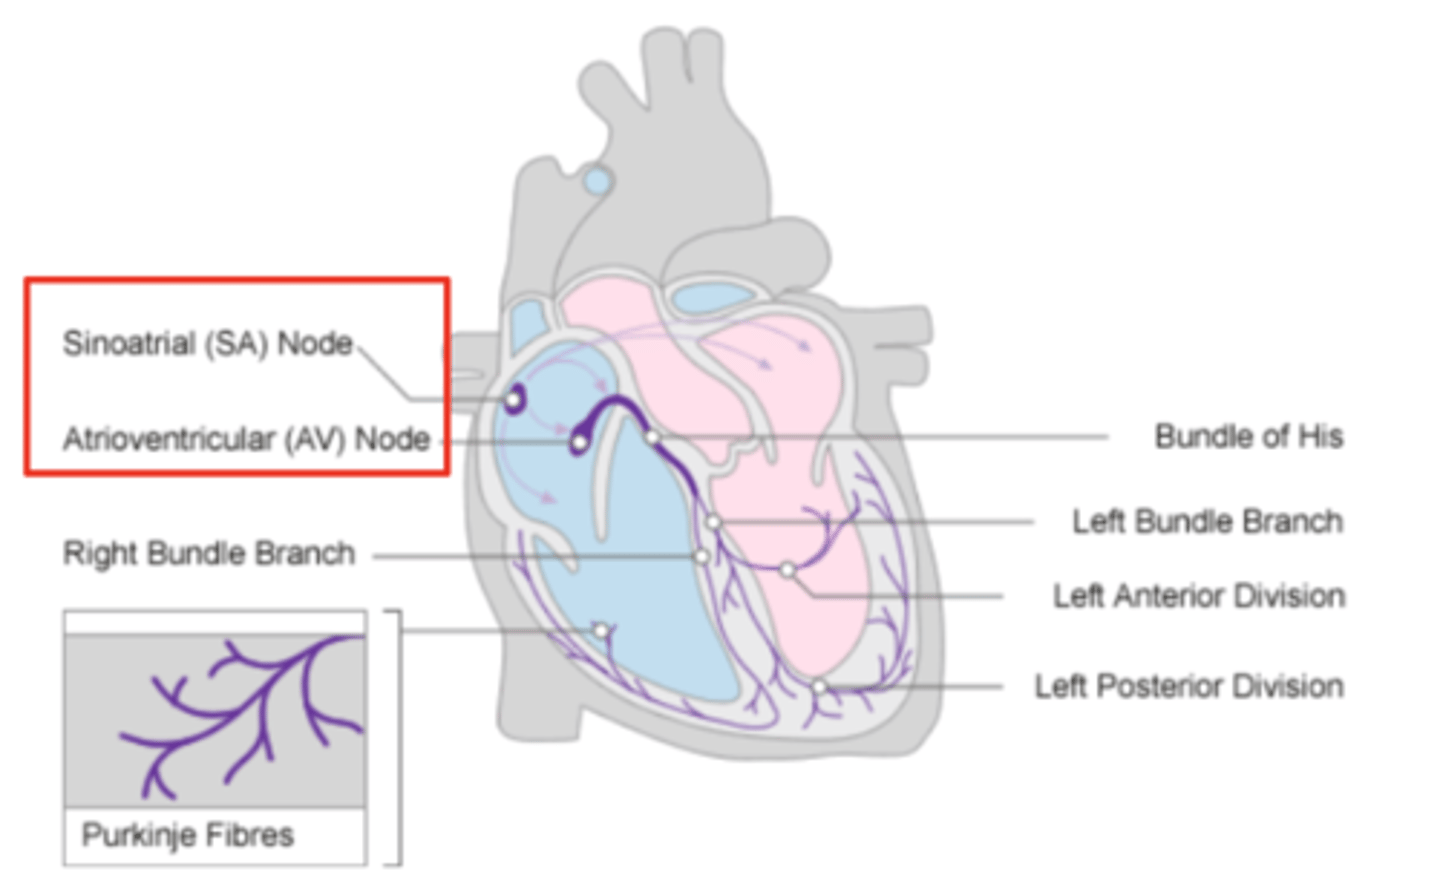

What are the two conduction nodes of the heart conduction system?

. SA node (sinoatrial node)

. AV node (atrioventicular node)

What is the function of the sinoatrial (SA) node?

Where is initiated the contraction of the SA node?

SVC (Superior Vena Cava)

passing through the atrium to the AV node

Where is the SA located?

upper wall of the right atrium,

at the junction where the superior vena cava enters

Where is the atrioventricular (AV) node located, and what follows it?

At the level of the atrioventricular septum,

AV node is followed by?

Bundle of Hiss that divides into two branches

Where does Bundle of Hiss ends?

Purkninje fibers

Describe the propagation of waves in the conduction system ?

. SA node sends the initial wave

Passes through the walls of the atria

. Ends at the AV node in the AV septum

. Travels along the Bundle of His

. Reaches Purkinje fibers in the walls of the ventricles

What role does the moderator band play in the conduction system?

Allows the wave to reach the papillary muscles, inducing their contraction simultaneously with that of the ventricles.

REMEMBER: PAPILLARY MUSCLES ACT THROUGH THE CHORDAE TENDINAE TO CONTROL THE TRICUSPID AND MITRAL VALVES.

What is the significance of the Bundle of His in heart conduction?

Branching to the right and left to ensure coordinated contraction of the ventricles.

What are the Purkinje fibers, and what is their function?

specialized conductive fibers in the walls of the ventricles that

facilitate rapid transmission of electrical impulses,

ensuring efficient and synchronized ventricular contraction.

How does the AV node contribute to heart rhythm?

Delays the electrical impulse from the SA node,

ensuring that the atria contract fully to transfer blood to the

ventricles before the ventricles contract.